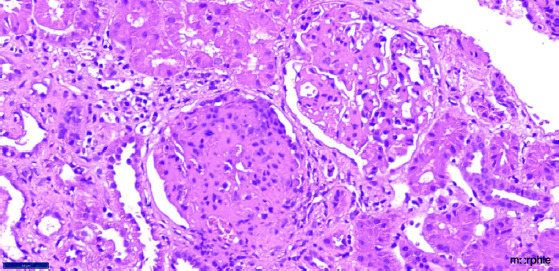

Collapsing glomerulopathy (CG), usually presents with renal dysfunction, hypertension and proteinuria. The etiology is uncertain, yet a number of associations, including many viral infections commonly have been reported. Tuberculosis (TB), one of the most common infections, is not known to cause CG. We report a case of severe renal dysfunction requiring dialysis who had collapsing glomerulopathy on biopsy and evidence of active pulmonary tuberculosis. Anti-tubercular therapy alone resulted in improvement in kidney function.

Abstract Image